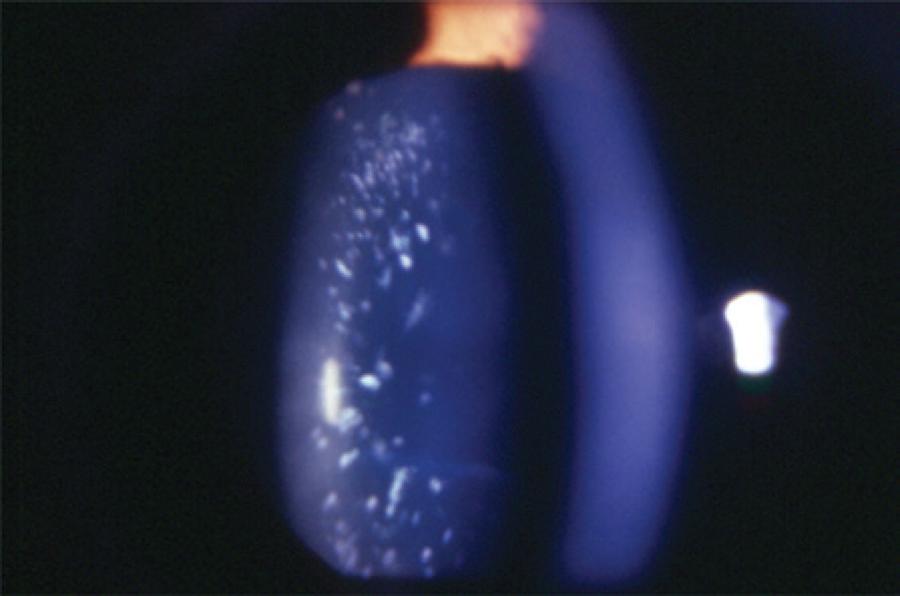

Cataract was classified according to the morphology as total (Figure 1), zonular, polar, capsular, and membranous. Zonular cataracts, which effect the fetal nucleus of the lens, were further classified as lamellar (Figure 2), pulverulent (Figure 3), nuclear (Figure 4), and sutural. According to the site of lens opacity, polar cataracts were classified as anterior, posterior, or pyramidal (Figure 5). Capsular cataracts were further classified as anterior, posterior, and lenticonus. When multiple morphological types of cataract co-exist in the same child or in the same eye, they are considered as mixed cataract.

Pediatric cataracts exhibit substantial heterogeneity. The opacity of the lens may affect the lens nucleus or alternatively the nucleus could remain transparent while the cortex or the lamellae surrounding the nucleus become opaque. The morphological diversity makes the morphological classification a challenging task. Additionally, there exists the possibility for overlapping morphologies. We found that zonular cataracts occurred with the highest frequency, in 72 (33.8%) patients. Among these cases, the lamellar subtype (Figure 2) was the most common (66.7%). Total cataract occurred in 66 (31.9%) patients (Figure 1).

Morphology or laterality of pediatric cataract may be indicative of its etiology. Hereditary cataracts display a variety of phenotypes, more frequently display a zonular morphology (Figure 3), and are usually bilateral. In most cases, the opacity of the lens caused by PFV are unilateral posterior subcapsular, which progress into complete opacity of the lens. We found that among the PFV patients, 52.94% had posterior subcapsular cataract (Table 4). Nuclear cataract (Figure 4) is usually detected at birth, whereas lamellar cataract (Figure 2) develops at a later stage and can be progressive. Visual prognosis may depend on the morphological type, with less favorable outcomes in cases of total cataracts(26).